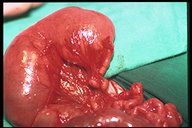

Multiple jejunal atresia. At surgeyr, jejunal atresia with dilated proximal pouch and varied length of small distal segments sausage-like are found. These segments connect to each other with cord-like (atretic part)-intestinal atresia type II.

Multiple jejunal atresia. A twisted calcified segment is found which may due to intrauterine volvulus caused atresia. Multiple "sausage-like" segments of jejunal atresia